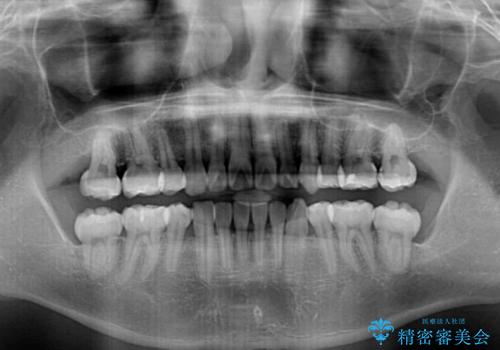

- 前歯の叢生と八重歯を気にして来院された患者様です。

叢生が強く、奥歯の咬合も左右差が大きかったため、上下左右4本を抜歯して、ワイヤー矯正を行うこととしました。

奥歯の咬み合わせを改善したいため、治療期間が長くなりましたが、患者様には辛抱強くお付き合いいただきました。

上下の正中を合わせることもでき、患者様には大変満足していただきました。